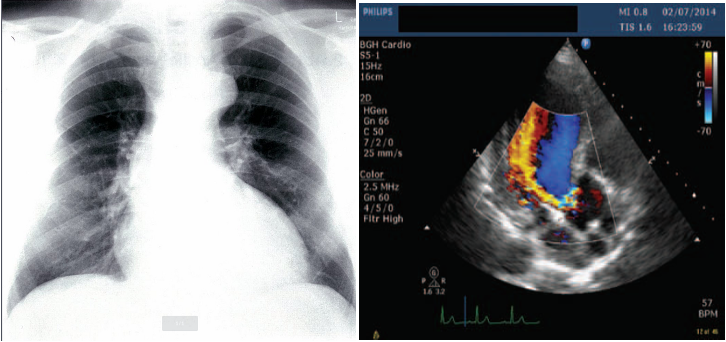

• Echocardiography and Doppler (TTE): First-line diagnostic tool: assess the severity: LV dilatation.

• CXR:

• Cardiomegaly: Dilating ascending aorta.

• Pulmonary edema (Acute AR) with normal cardiac size.; crepitation

Findings specific to acute AR: CXR

• Reduced cardiac output.

• Elevated end-diastolic left ventricular pressure.

• Early mitral valve closing.

• (Regurgitant jet is diagnostic).

Imaging

A. Echocardiogram:

• Allows visualization of the origin of the regurgitant jet and its width, detection of aortic valve pathology and ventricular hypertrophy.

B. CXR:

• May demonstrate cardiomegaly.

• Dilated ascending aorta.

• Calcification may be seen.

A 30-year-old woman presented with shortness of breath on exertion and occasional chest pain. Does not use tobacco, alcohol, or illicit drugs. She immigrated from Peru two years ago with her family. Her temperature is 36.4°C; pulse is 115/min, respirations are 24/min, and blood pressure is 130/60 mm Hg. Physical examination shows pulsations of the nail bed. Cardiac examination shows an abnormal heart sound over the left sternal border on auscultation (see image below). Which of the following maneuvers will likely decrease the intensity of this heart sound?